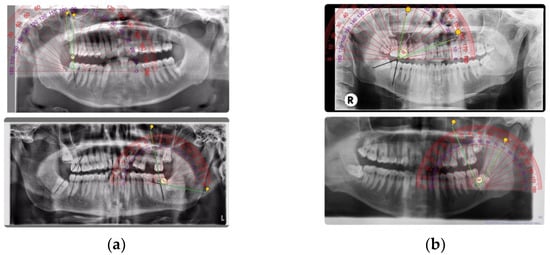

The angulation of the impacted third molar was documented based on Winter’s classification regarding the angle formed between the intersected longitudinal axes of the second and third molars, namely vertical impaction (10° to −10°), mesioangular impaction (11° to 79°), horizontal impaction (80° to 100°), distoangular impaction (−11° to −79°), others (111° to −80°), and buccolingual impaction (any tooth oriented in a buccolingual direction with crown overlapping the roots) [17]. The axis of the teeth was measured on panoramic radiographs obtained from the patients by using a ruler and compass (Figure 1a,b).

Figure 1. (a) Vertical and horizontal impaction; (b) Mesioangular and distoangular impaction.